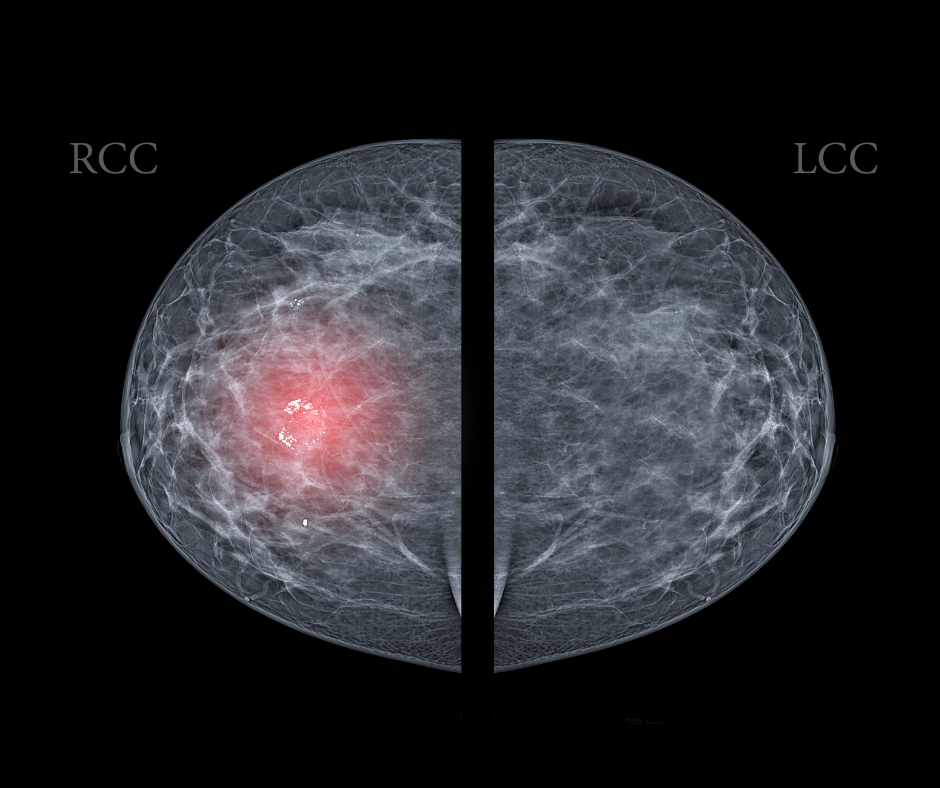

Emerging research suggests a higher prevalence of positive breast arterial calcification (BAC) rates among Hispanic and Black women, and a lower rate of BAC in women with dense breasts or breast implants.

Women who had enhancing lesions associated with low-energy findings were more than twice as likely to have malignancy in comparison to those who had enhancing lesions without low-energy findings.

The review of breast cancer screening guidelines from the United States and abroad summarized current recommendations on modalities, intervals, and screening age considerations.